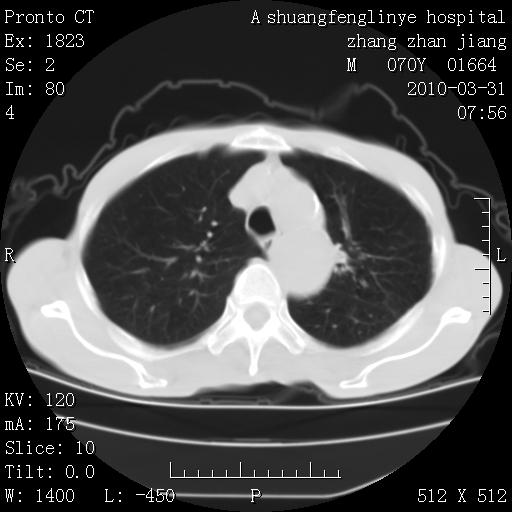

双上肺继发型tb并左上空洞形成,主动脉冠脉钙化。

1)两肺上叶继发性肺结核并左肺上叶空洞形成。2)冠状动脉及主动脉钙化。